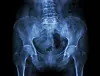

röntgen, osteoporoos

Osteoporoos ehk luuhõrenemine on skeleti haigus, mille puhul väheneb luude mass ja häirub luukoe struktuur. Luud muutuvad hõredaks ning murduvad kergesti. Haiguse algstaadiumis erilisi sümptomeid ei ole, võivad esineda tagasihoidlikud valud seljas või puusas. Sageli on esimeseks märgiks luumurru tekkimine ilma erilise tugeva traumata. Luu võib murduda iseenesest, mis on sageli iseloomulik lülisamba murdude puhul vanematel inimestel.